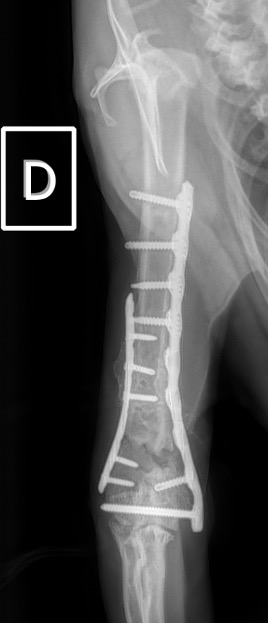

Notre préférence va vers le placement de deux plaques humérales : une médiale de la plus grande taille possible et l’autre latérale, généralement d’une taille inférieure à la première. Dans l’exemple 1 (chat européen), une plaque de 2 mm est utilisée médialement et une plaque de 1,5 mm latéralement. Dans l’exemple 2 (chien Malinois), une plaque de 3,5 mm est utilisée médialement et une plaque de 2,7 mm latéralement.

Exemple 2 :

Figure 5 : Post-Op Immédiat